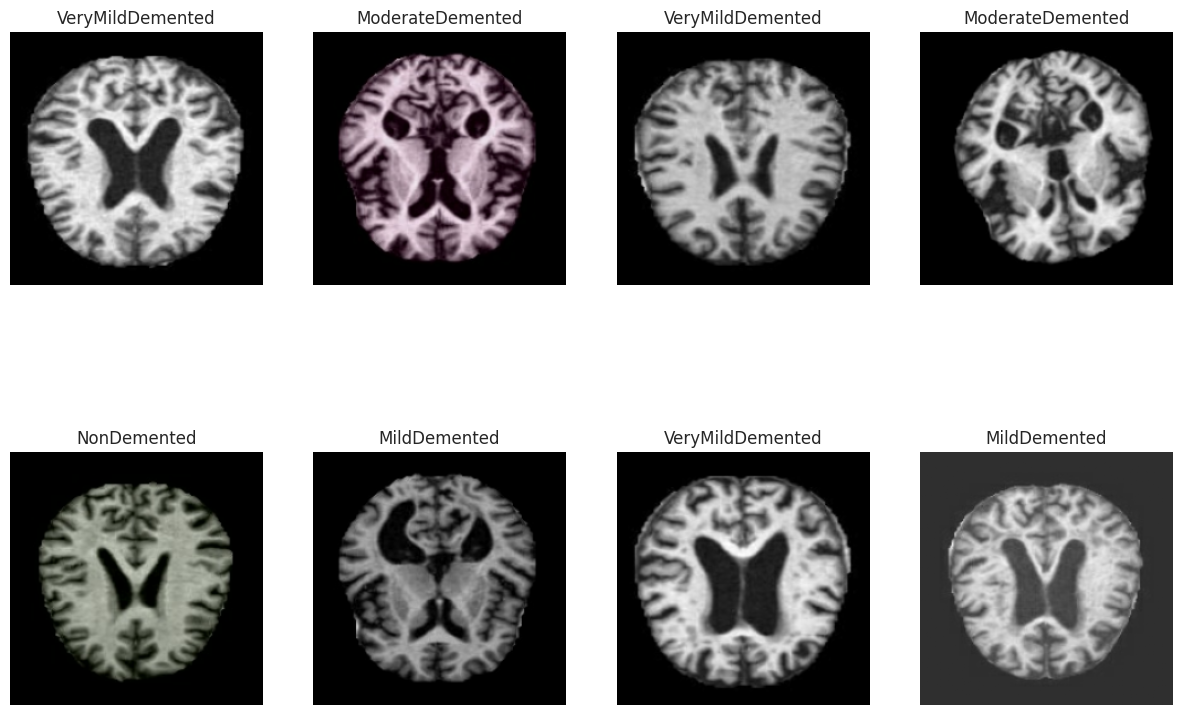

4.3数据可视化

从验证数据集中随机抽取一批MRI图像样本进行可视化展示。对于阿尔茨海默病诊断研究,观察原始脑部MRI图像的质量和特征非常重要,这能帮助我们理解数据特点并检查预处理是否正确。

# 从验证数据集中获取一个批次的图像和标签样本

# iter()将数据集转换为迭代器,next()获取下一个批次

img_sample, label_sample = next(iter(val_set))

# 创建2行4列的子图网格,用于展示8个MRI图像样本

# figsize=(15, 10)设置整个图形大小为15x10英寸

fig, axis = plt.subplots(2, 4, figsize=(15, 10))

# 遍历所有子图(共8个),在每个子图中显示一张MRI图像

for i, ax in enumerate(axis.flat):

# 将第i个图像样本从TensorFlow张量转换为numpy数组

# 因为matplotlib的imshow函数需要numpy数组格式

img = img_sample[i].numpy()

# 在当前子图中显示MRI图像

ax.imshow(img)

# 关闭坐标轴显示,使图像更清晰

# MRI医学图像通常不需要显示坐标刻度

ax.axis('off')

# 设置子图标题,显示对应的疾病类别名称

# label_sample[i]是one-hot编码格式,使用argmax()找到值为1的位置索引

# 通过label_map字典将数字索引转换为可读的类别名称

ax.set(title=f"{label_map[np.array(label_sample[i]).argmax()]}")

# 显示完整图形

plt.show()